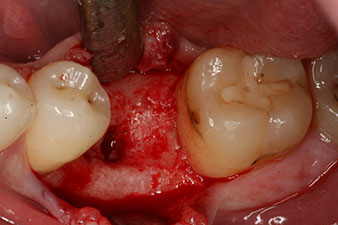

The implant was placed as planned after thorough removal of the granulation tissue (blueSky, bredent).

The torque used for the machine-driven placement was 43 Ncm. In addition, after screwing a measuring post (SmartPeg) specially matched to the implant, the ISQ value was measured with the probe of the W&H Osstell ISQ module.

These values could have indicated open healing or even immediate restoration. Due to the insufficient crestal bone volume at the implant, the region was augmented with the bone chips collected during preparation of the implant bed and sutured to exclude saliva.